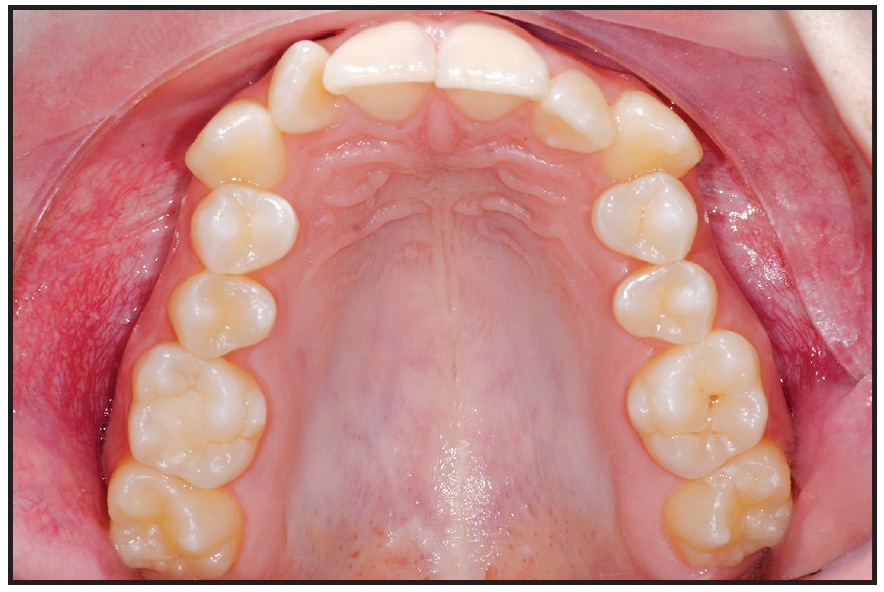

A 17-year-old female patient presented with a narrow maxilla (Fig. 5). We chose a Quadexpander with two 9mm × 2mm anterior paramedian screws and two 9mm × 2mm posterior screws between the second premolars and first molars to perform MARPE without surgery (Figs. 6,7).

The patient was instructed to turn the expander .2mm per day. Five days after the initial activation, two additional 90° turns were performed to assess the mobility of the maxillary halves. After 27 days, about 6mm of expansion had been achieved (Fig. 8). The expander was left passively in place for 10 months to maintain the expansion during orthodontic treatment with a fixed appliance.